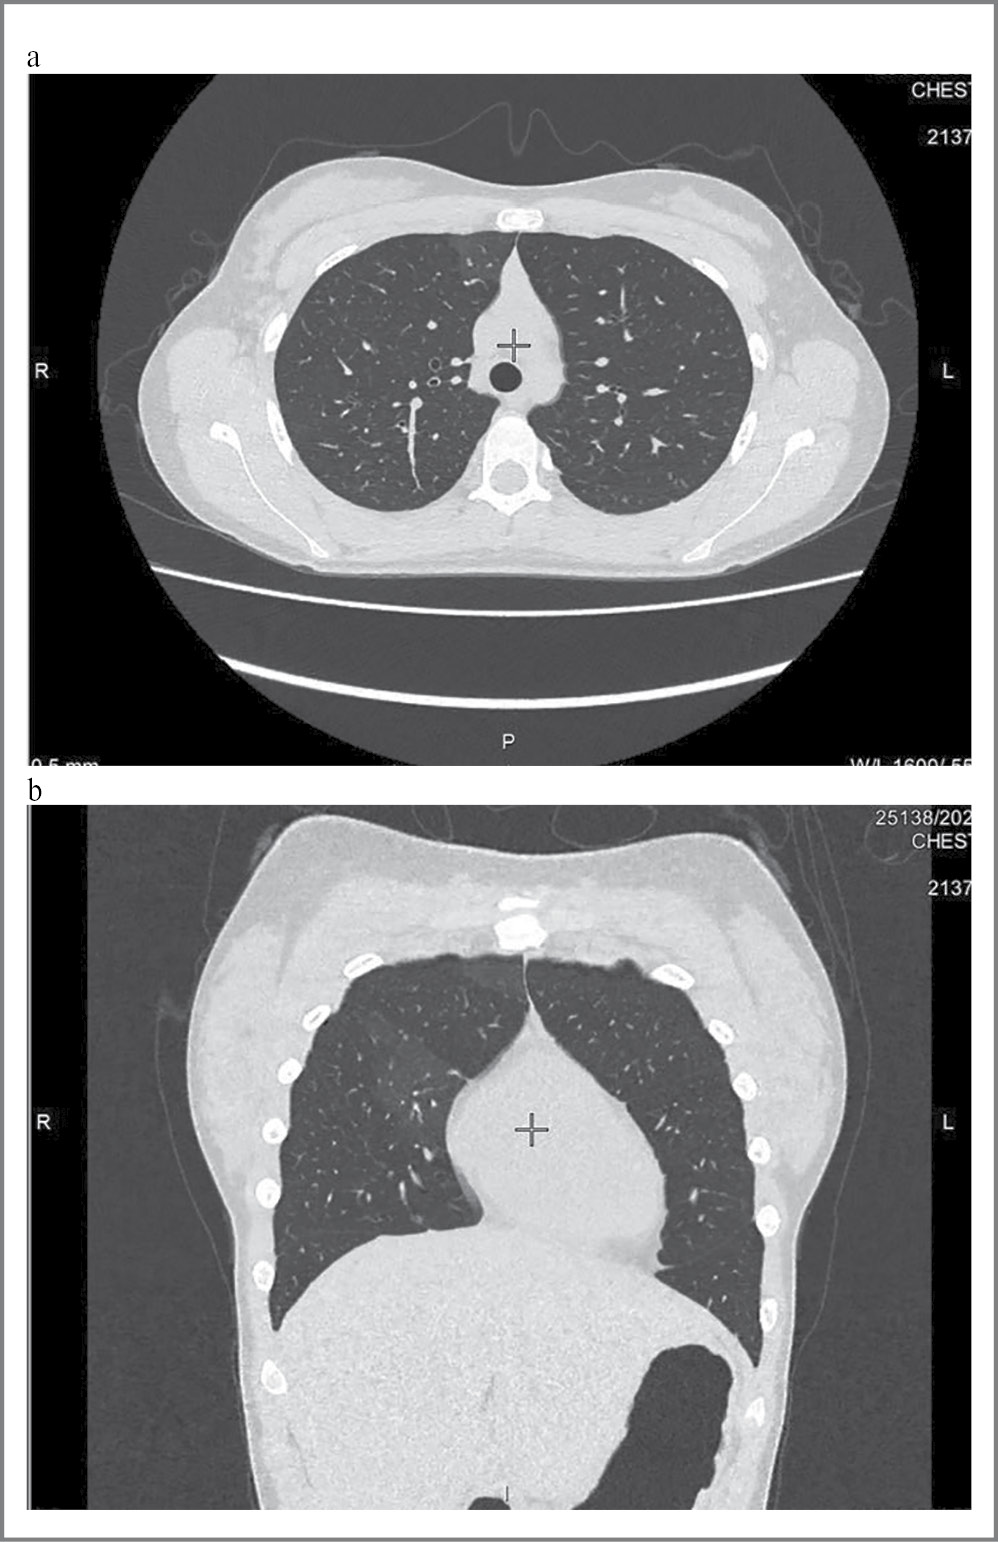

Компьютерная томография органов грудной клетки (КТ ОГК): участки полисегментарного уплотнения легочной ткани в обоих легких (в SIII, SV,VI справа и SVI слева определяются неправильной формы зоны уплотнения легочной ткани по типу «матового стекла»); рис. 1, a, b.

Рис. 1. КТ органов грудной клетки: a – аксиальный срез; b – корональный срез.

После выявления изменений на КТ ОГК проведена дополнительная беседа с подростком, в ходе которой выяснилось, что девочка в течение 4 лет (с 2017 г.) использует вейпинг. Пациентка тщательно скрывала вредную привычку от родителей и врачей, что затруднило сбор анамнеза при поступлении.

КТ ОГК: патологических изменений в легких не выявлено. На фоне проводимой терапии отмечается разрешение участков уплотнения легочной ткани по типу «матового стекла».

В данном клиническом случае поставить верный диагноз девочке-подростку с предрасположенностью к аллергическим состояниям удалось благодаря дополнительному повторному тщательному сбору анамнеза, т.к. выявленные изменения на КТ легких не были характерны для бронхиальной астмы. На фоне проводимой терапии наблюдалась отчетливая положительная динамика как клинической картины, так и КТ-картины легких.